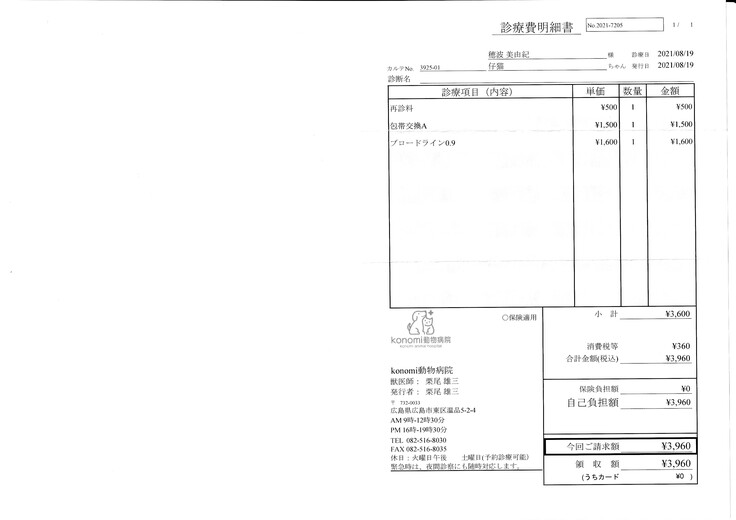

明細書

①入院費用

②退院後の飼育と治療

治療は続いていますが、これまでにかかった費用の一部を皆さまに助けて頂きたく、宜しくお願い致します。

8月24日にスクリューが皮膚から出ていた為、プレートの除く手術を行いました。

人間で例えると右足首は完治しませんが、歩行には問題がないため再手術は行いませんでした。